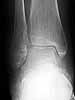

58 y/o female, had ankle sprain 3 months ago. First avulsion fracture on the tip of fibula was diagnosed and cast was applied for four weeks. After cast removal pain and swelling did not subside.

Now has mild swelling at ankle. Walks with cruches, weight bearing is not possible due to pain.

I think there was a nondisplaced talar neck fracture with complicated by AVN.

Current X-ray shows sclerosis of talar body, destruction at talar dome. MRI shows diffuse swelling in talus (interesting where comes the swelling if there is avascularity?). CT does not surely confirm fracture but shows diffuse osteoporosis in tarsal bones.